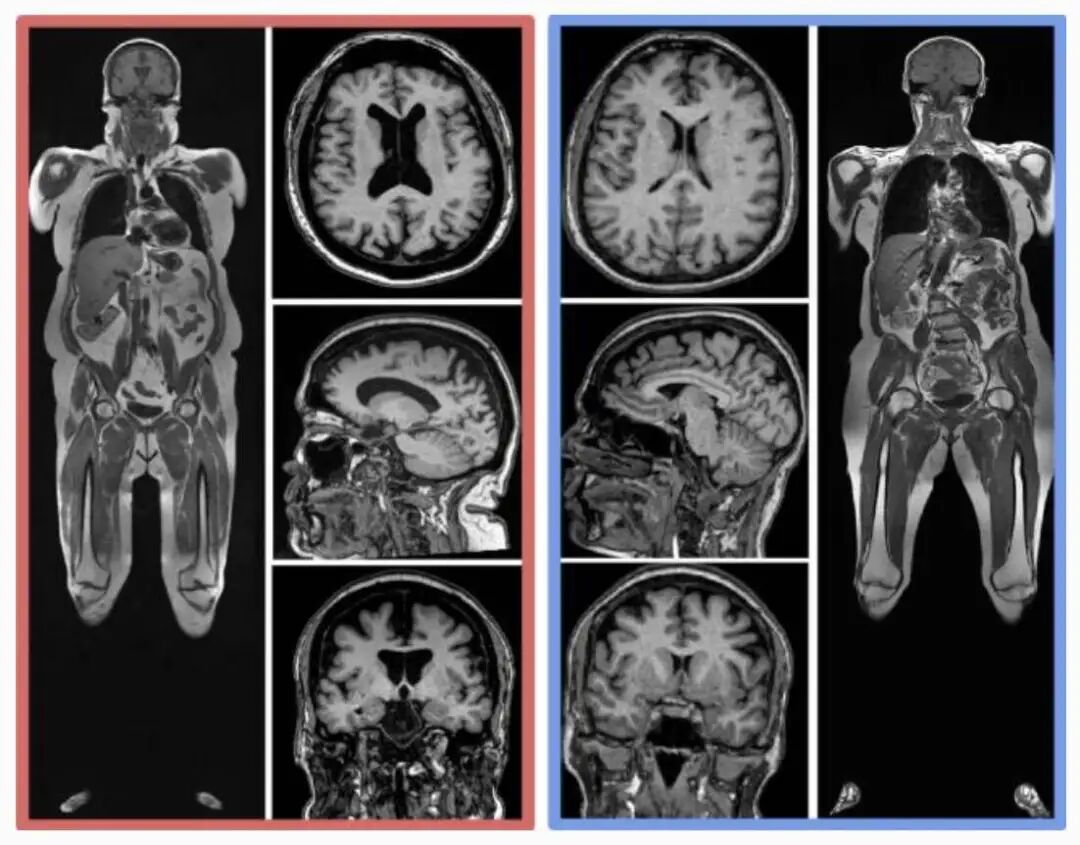

同样年龄的人,腹部脂肪(皮下和内脏)更多,脑部图像显示出更小的脑容量。

2023年8月,来自美国华盛顿大学等10个科研机构,纳入了10001名参与者,经过全身核磁、计算机深度学习、回归分析等一通复杂操作后,谨慎得出了结论:内脏脂肪越多,大脑(灰质、白质等)越小。